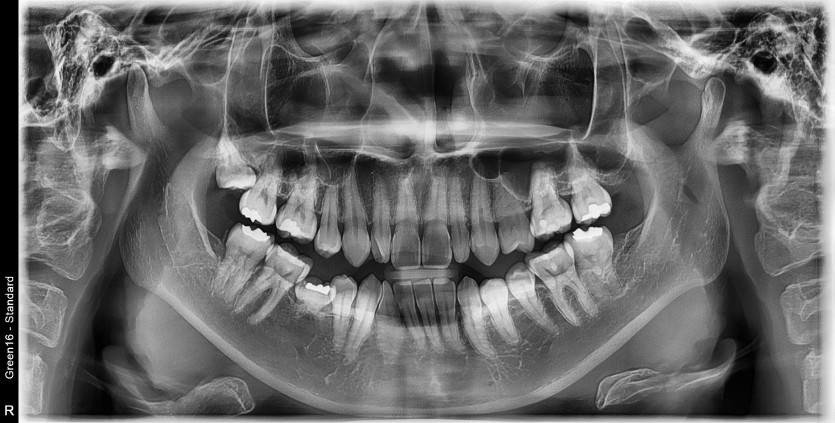

#18 사랑니 발치

구강 외과 전문의가 당일 발치했습니다.